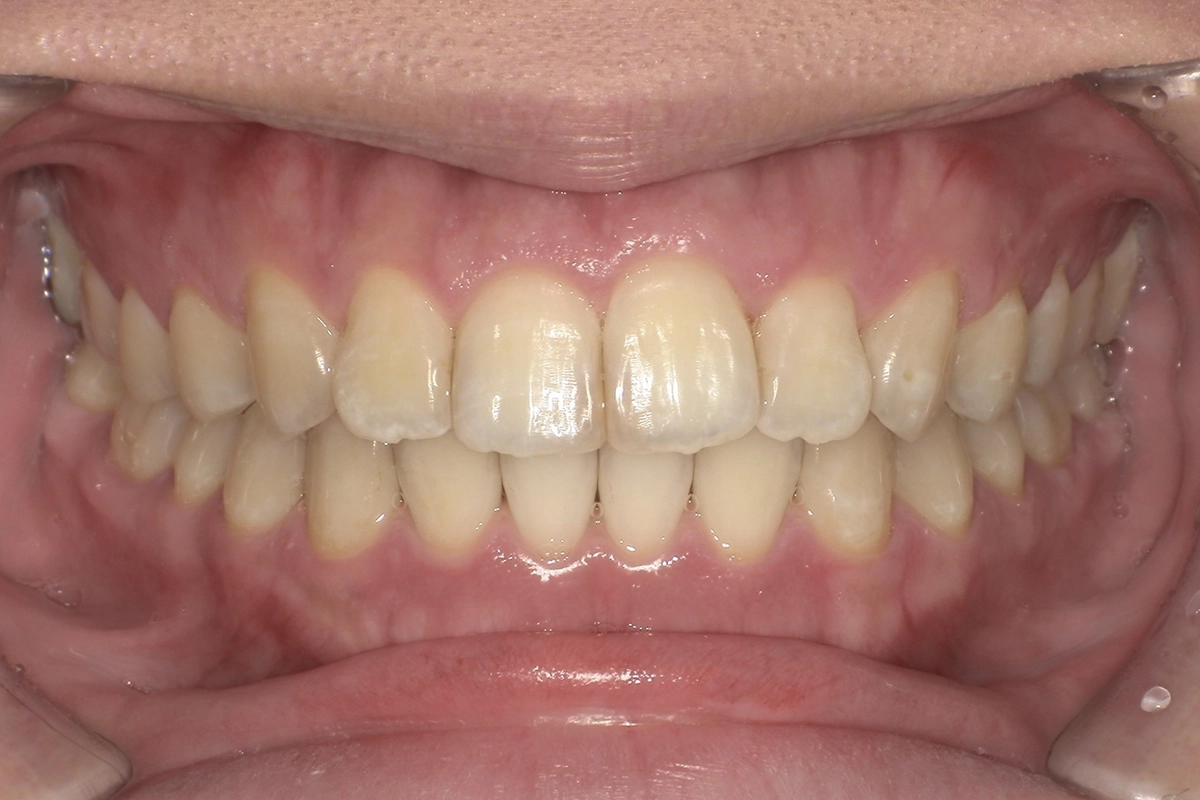

正面

after

噛み合わせの改善

上下の前歯がしっかり接触するようになり、前歯で食べ物を噛み切れるようになりました。これにより奥歯への過度な負担も軽減されています。

見た目の改善

前方に飛び出していた歯が歯列の中に収まり、滑らかなアーチを描くようになりました。